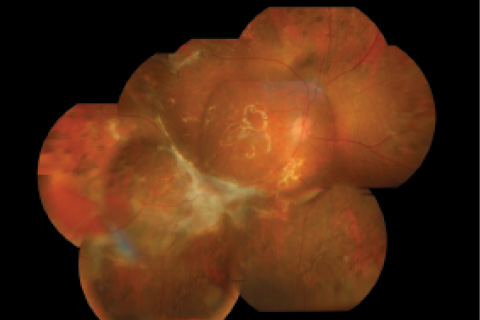

Figure 4. Another photo montage taken after the patient’s final surgery during which the ERM was removed.

We advised another surgery, which was performed the next day (Video 3). During this procedure, the ERM was removed using forceps. The postoperative recovery was uneventful, and the patient recovered about 6/60 visual acuity at 1 month follow-up and 6/24 at 3 months follow-up (Figure 4). She retained this visual acuity after silicone oil removal 4 months postoperatively.